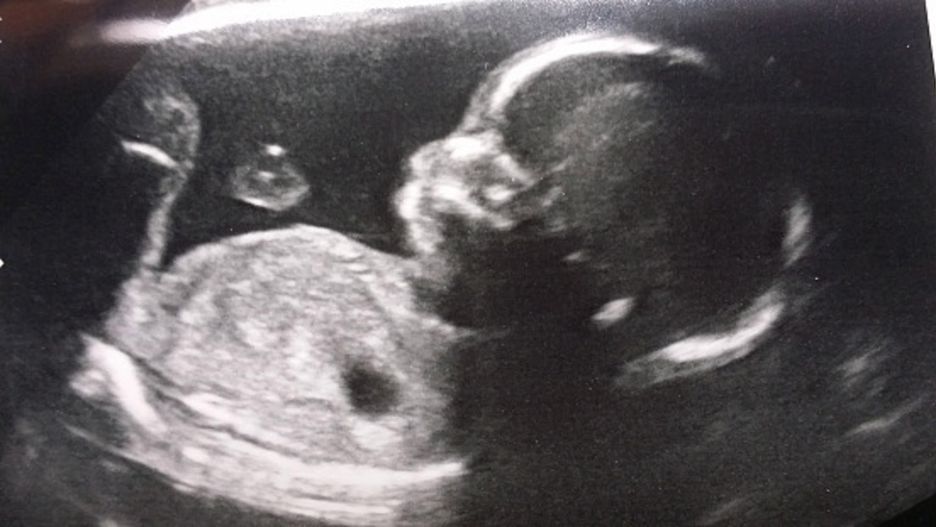

Ułożenie dzieckaUłożenie dziecka

Źródło zdjęć: © GettyImages